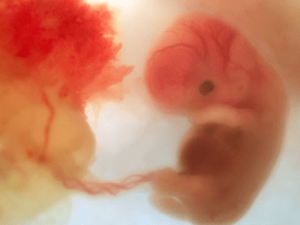

Trong vòng 24 giờ sau khi thụ tinh, trứng sẽ nhanh chóng phân chia thành nhiều tế bào và tạo thành phôi thai. Cùng Docosan tìm hiểu về sự phát triển của thai nhi trong từng giai đoạn của thai kỳ. 1. Thời điểm bắt đầu mang thai Ngày bắt đầu mang thai được tính […]